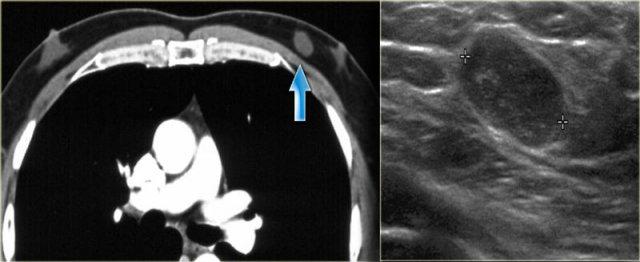

Bên trái là gynecomastia một bên.

Đây là phát hiện tình cờ trên CT được thực hiện vì một lý do khác.

Theo định nghĩa, gynecomastia là mô dưới quầng vú có kích thước từ 2 cm trở lên ở nam giới không béo phì.

Đây là một phát hiện ‘bình thường’ thường gặp, được ghi nhận ở 55% nam giới khi khám nghiệm tử thi.

Đỉnh tần suất mắc bệnh là ở độ tuổi 60 – 69.

Tình trạng này có ý nghĩa lâm sàng khi xuất hiện mới hoặc có triệu chứng.

Bên trái là hình ảnh của một bệnh nhân có hai tổn thương di căn từ ung thư biểu mô tế bào nhỏ của phổi.

Liposarcoma

Liposarcoma là một loại sarcoma hiếm gặp.

Biểu hiện là một khối phát triển chậm, gây đau.

Thường có tỷ trọng nước và không điển hình cho tổn thương chứa mỡ.

Trên hình CT bên trái, có thể thấy tỷ trọng của tổn thương được xác định là liposarcoma.